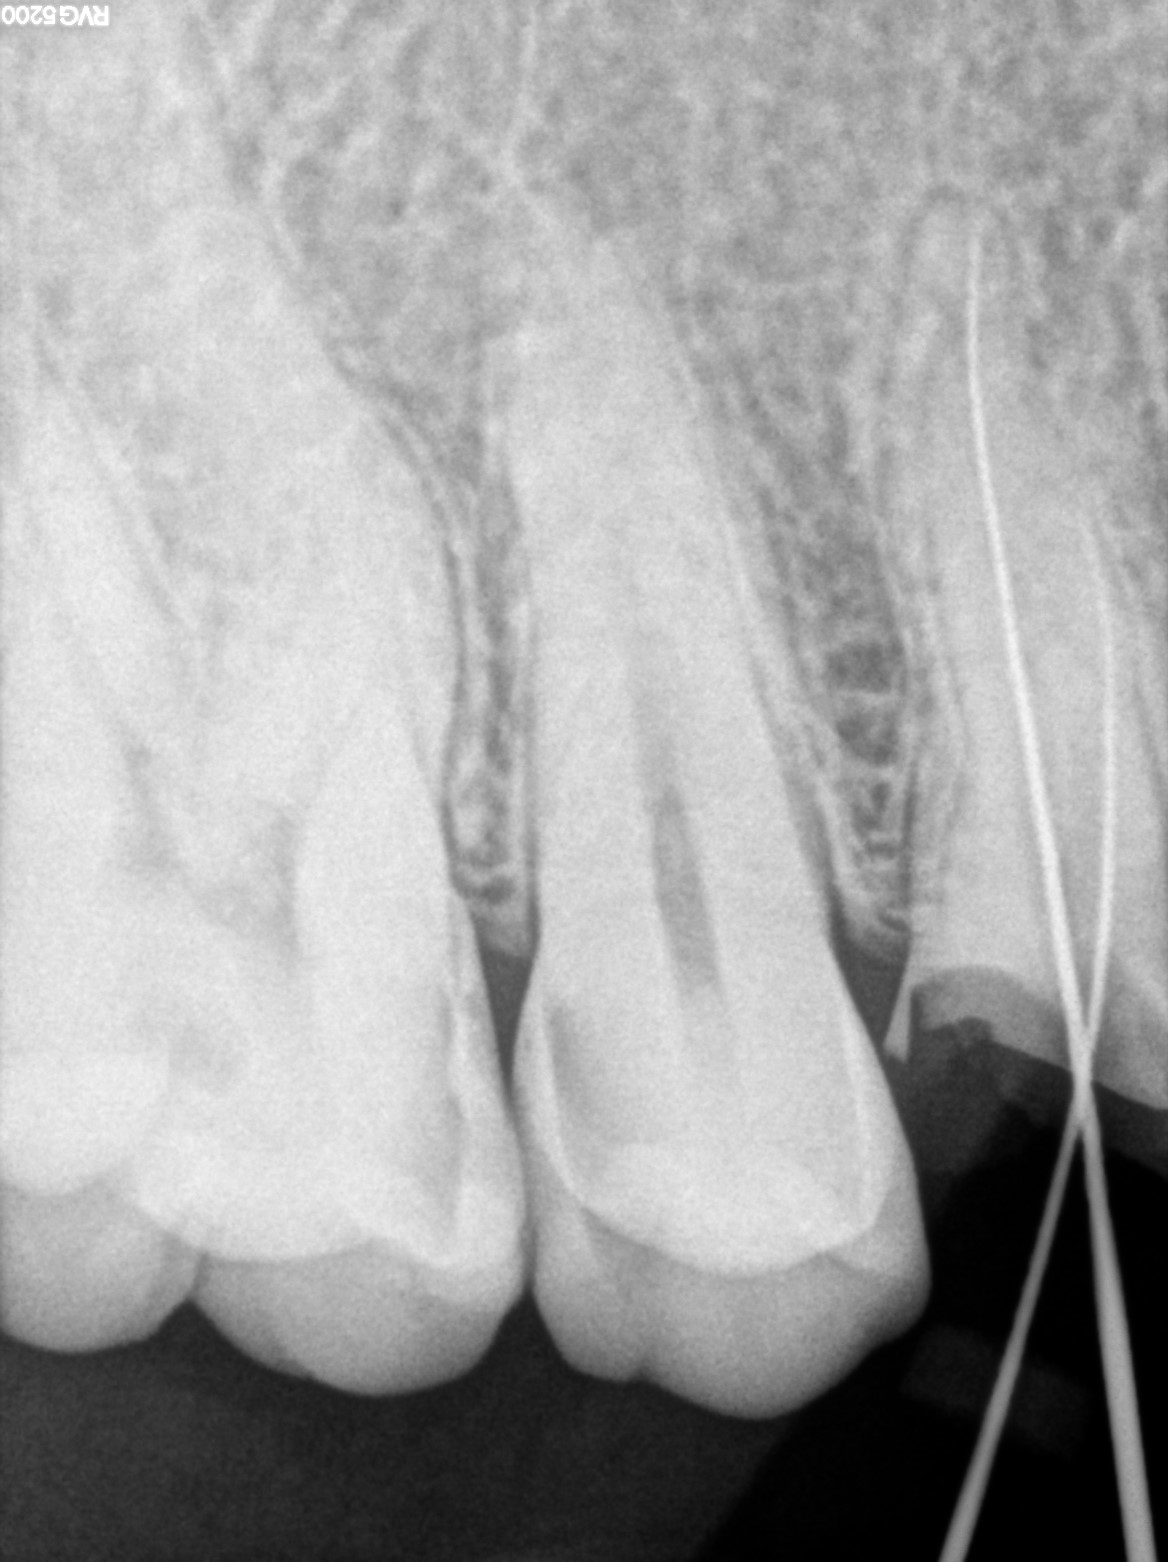

Dental Radiographs FHIR: DocumentReference · LOINC 24641-7

FHIR Bundle

xray_1772642539_0.jpg

24641-7

xray_1772642477_1.jpg

R55.jpg

xray_1770998647_1.jpg

R57.jpg

xray_1770476620_0.jpg

xray_1770998647_0.jpg

xray_1771259343_0.jpg

R56.jpg

xray_1772120353_0.jpg

R62.jpg

xray_1772642477_0.jpg